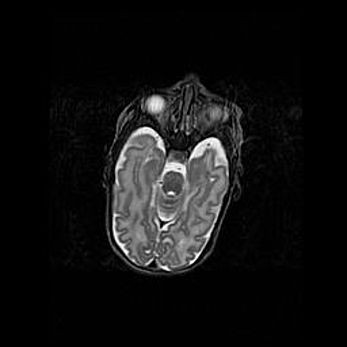

Лейкомаляция с кистозно-глиозной дегенерацией головного мозга.

Возраст: 2 месяца 25 дней

Вес: 6400 г

Окружность головы: 40 см

Срок гестации: 41 неделя

Лейкомаляцию относят к ишемически-гипоксическим повреждениям головного мозга, диагностируемым у новорожденных. При лейкомаляции в головном мозге обнаруживают очаги некроза, возникшие после тяжелой гипоксии и нарушения кровотока. В процессе морфогенеза очаги проходят три стадии: 1) развития некроза, 2) резорбции и 3) формирования глиозного рубца или кисты. Перивентрикулярная лейкомаляция (ПЛ) встречается примерно в 12% случаев среди новорожденных, обычно – у недоношенных детей, причем, частота ее зависит от массы, с которой младенец появился на свет. Наибольшее число малышей страдает лейкомаляцией, если масса при рождении 1500-2500 г.